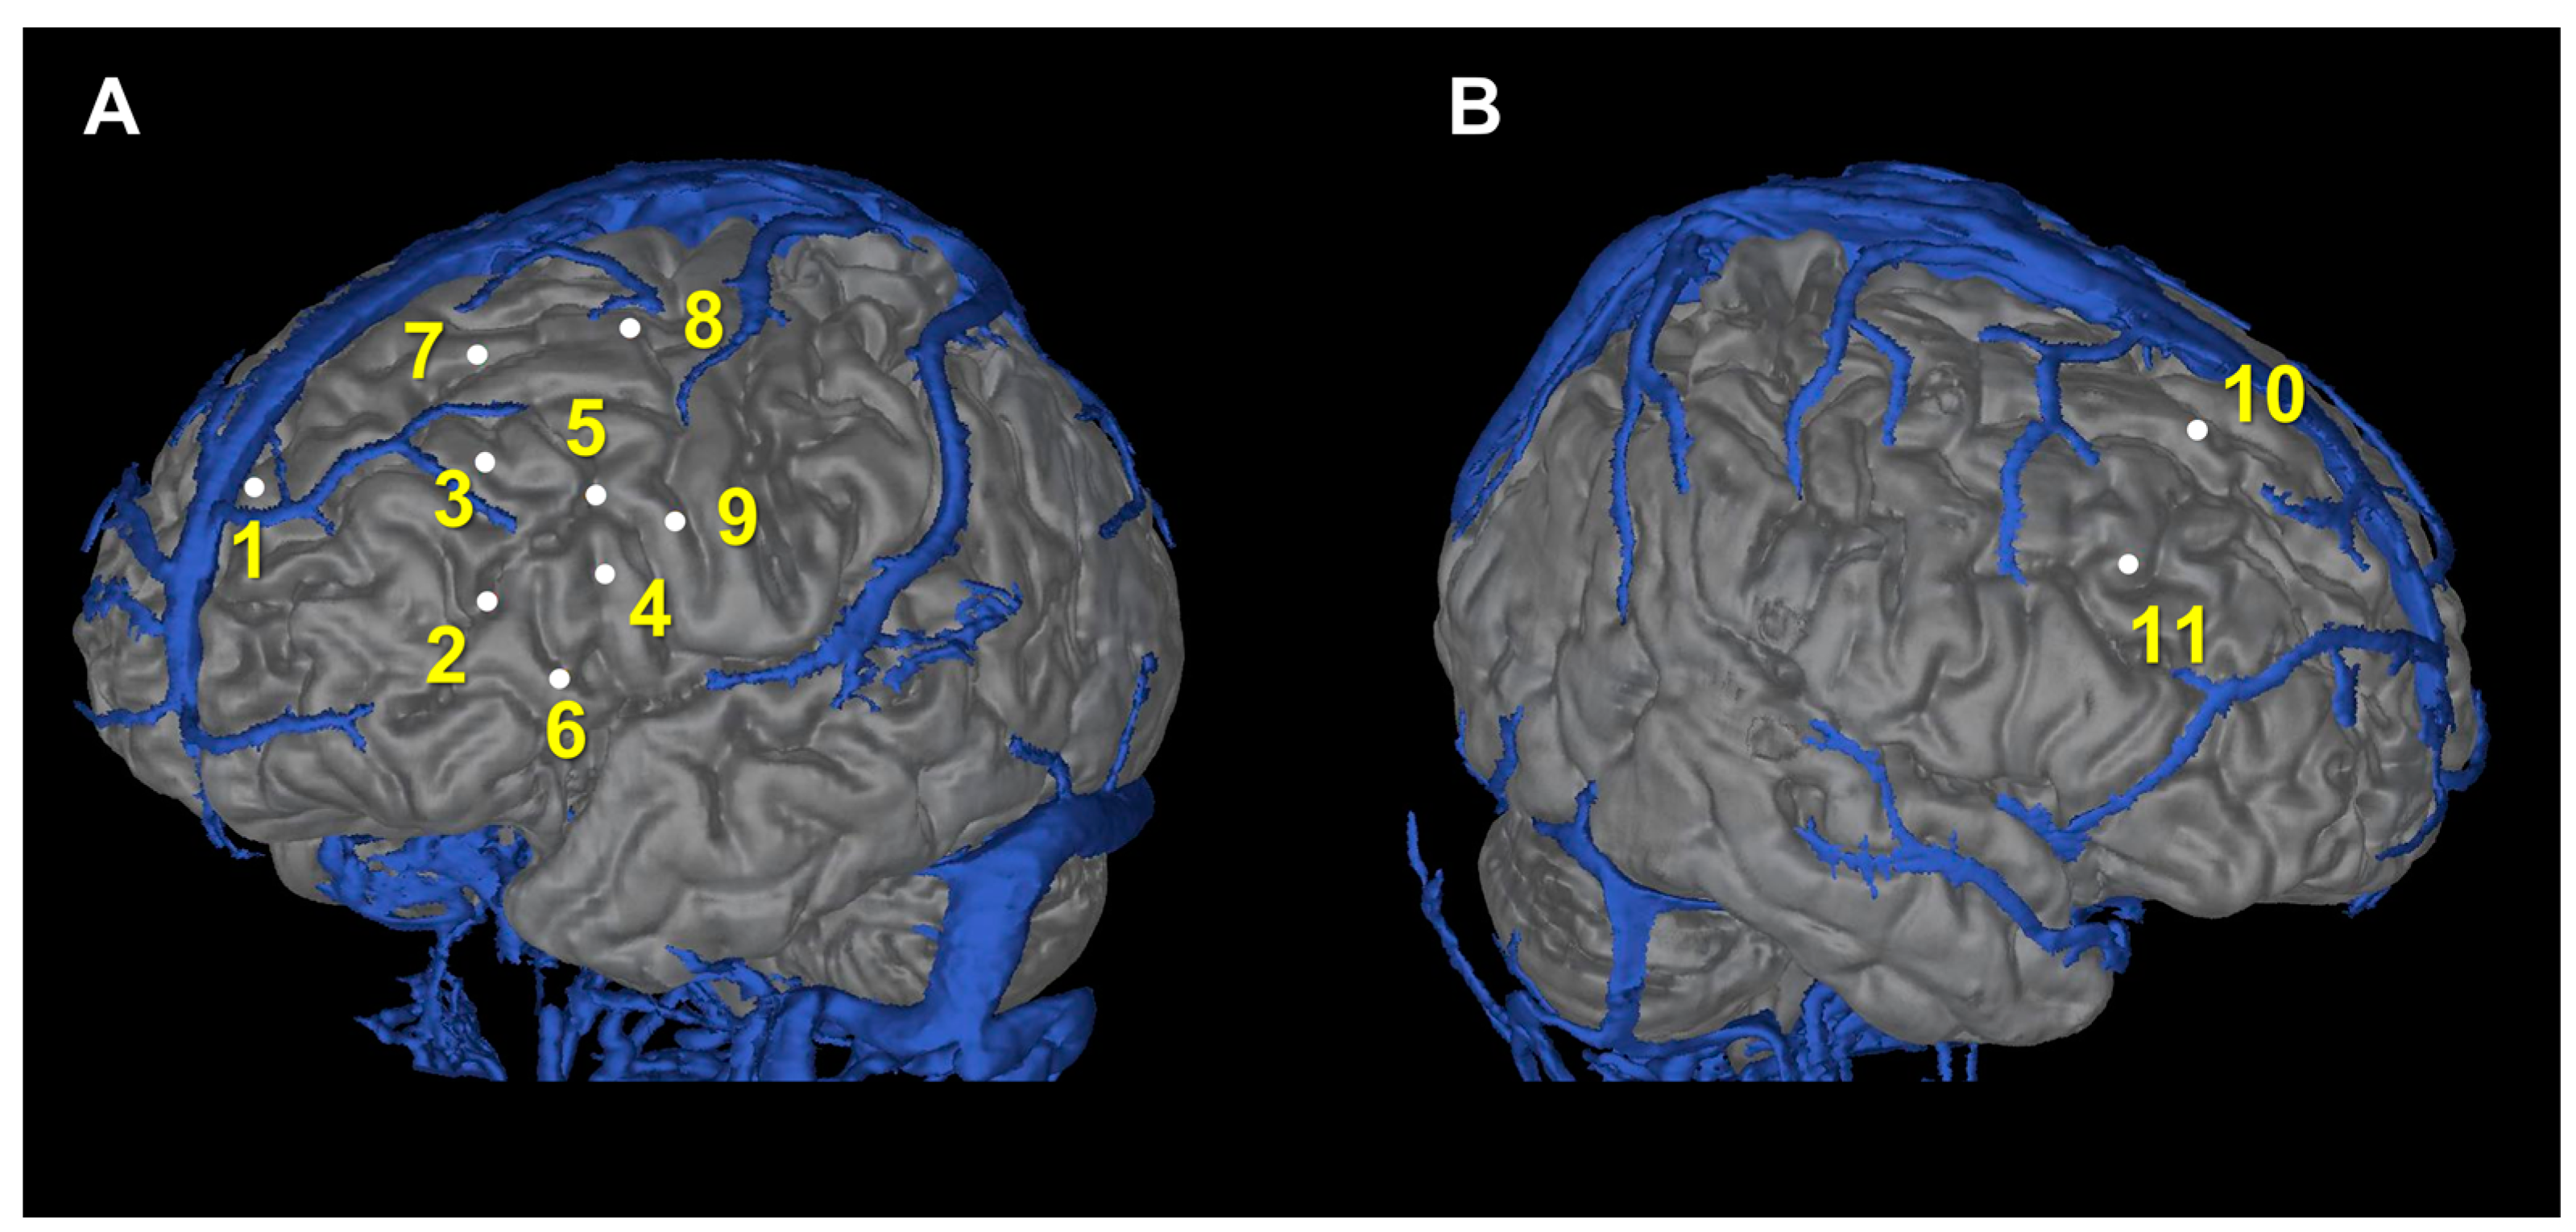

| Electrode # | Side | Entry | Target |

|---|---|---|---|

| 1 | Left | SFG | anterior Orb |

| 2 | Left | IFG | posterior Orb |

| 3 | Left | MFG | anterior Cing |

| 4 | Left | IFG | anterior Cing |

| 5 | Left | FEF | middle Cing |

| 6 | Left | IFG | middle Cing |

| 7 | Left | anterior SFG | SMA |

| 8 | Left | posterior SFG | SMA |

| 9 | Left | PreCG | insula |

| 10 | Right | SFG | SMA |

| 11 | Right | MFG | middle Cing |